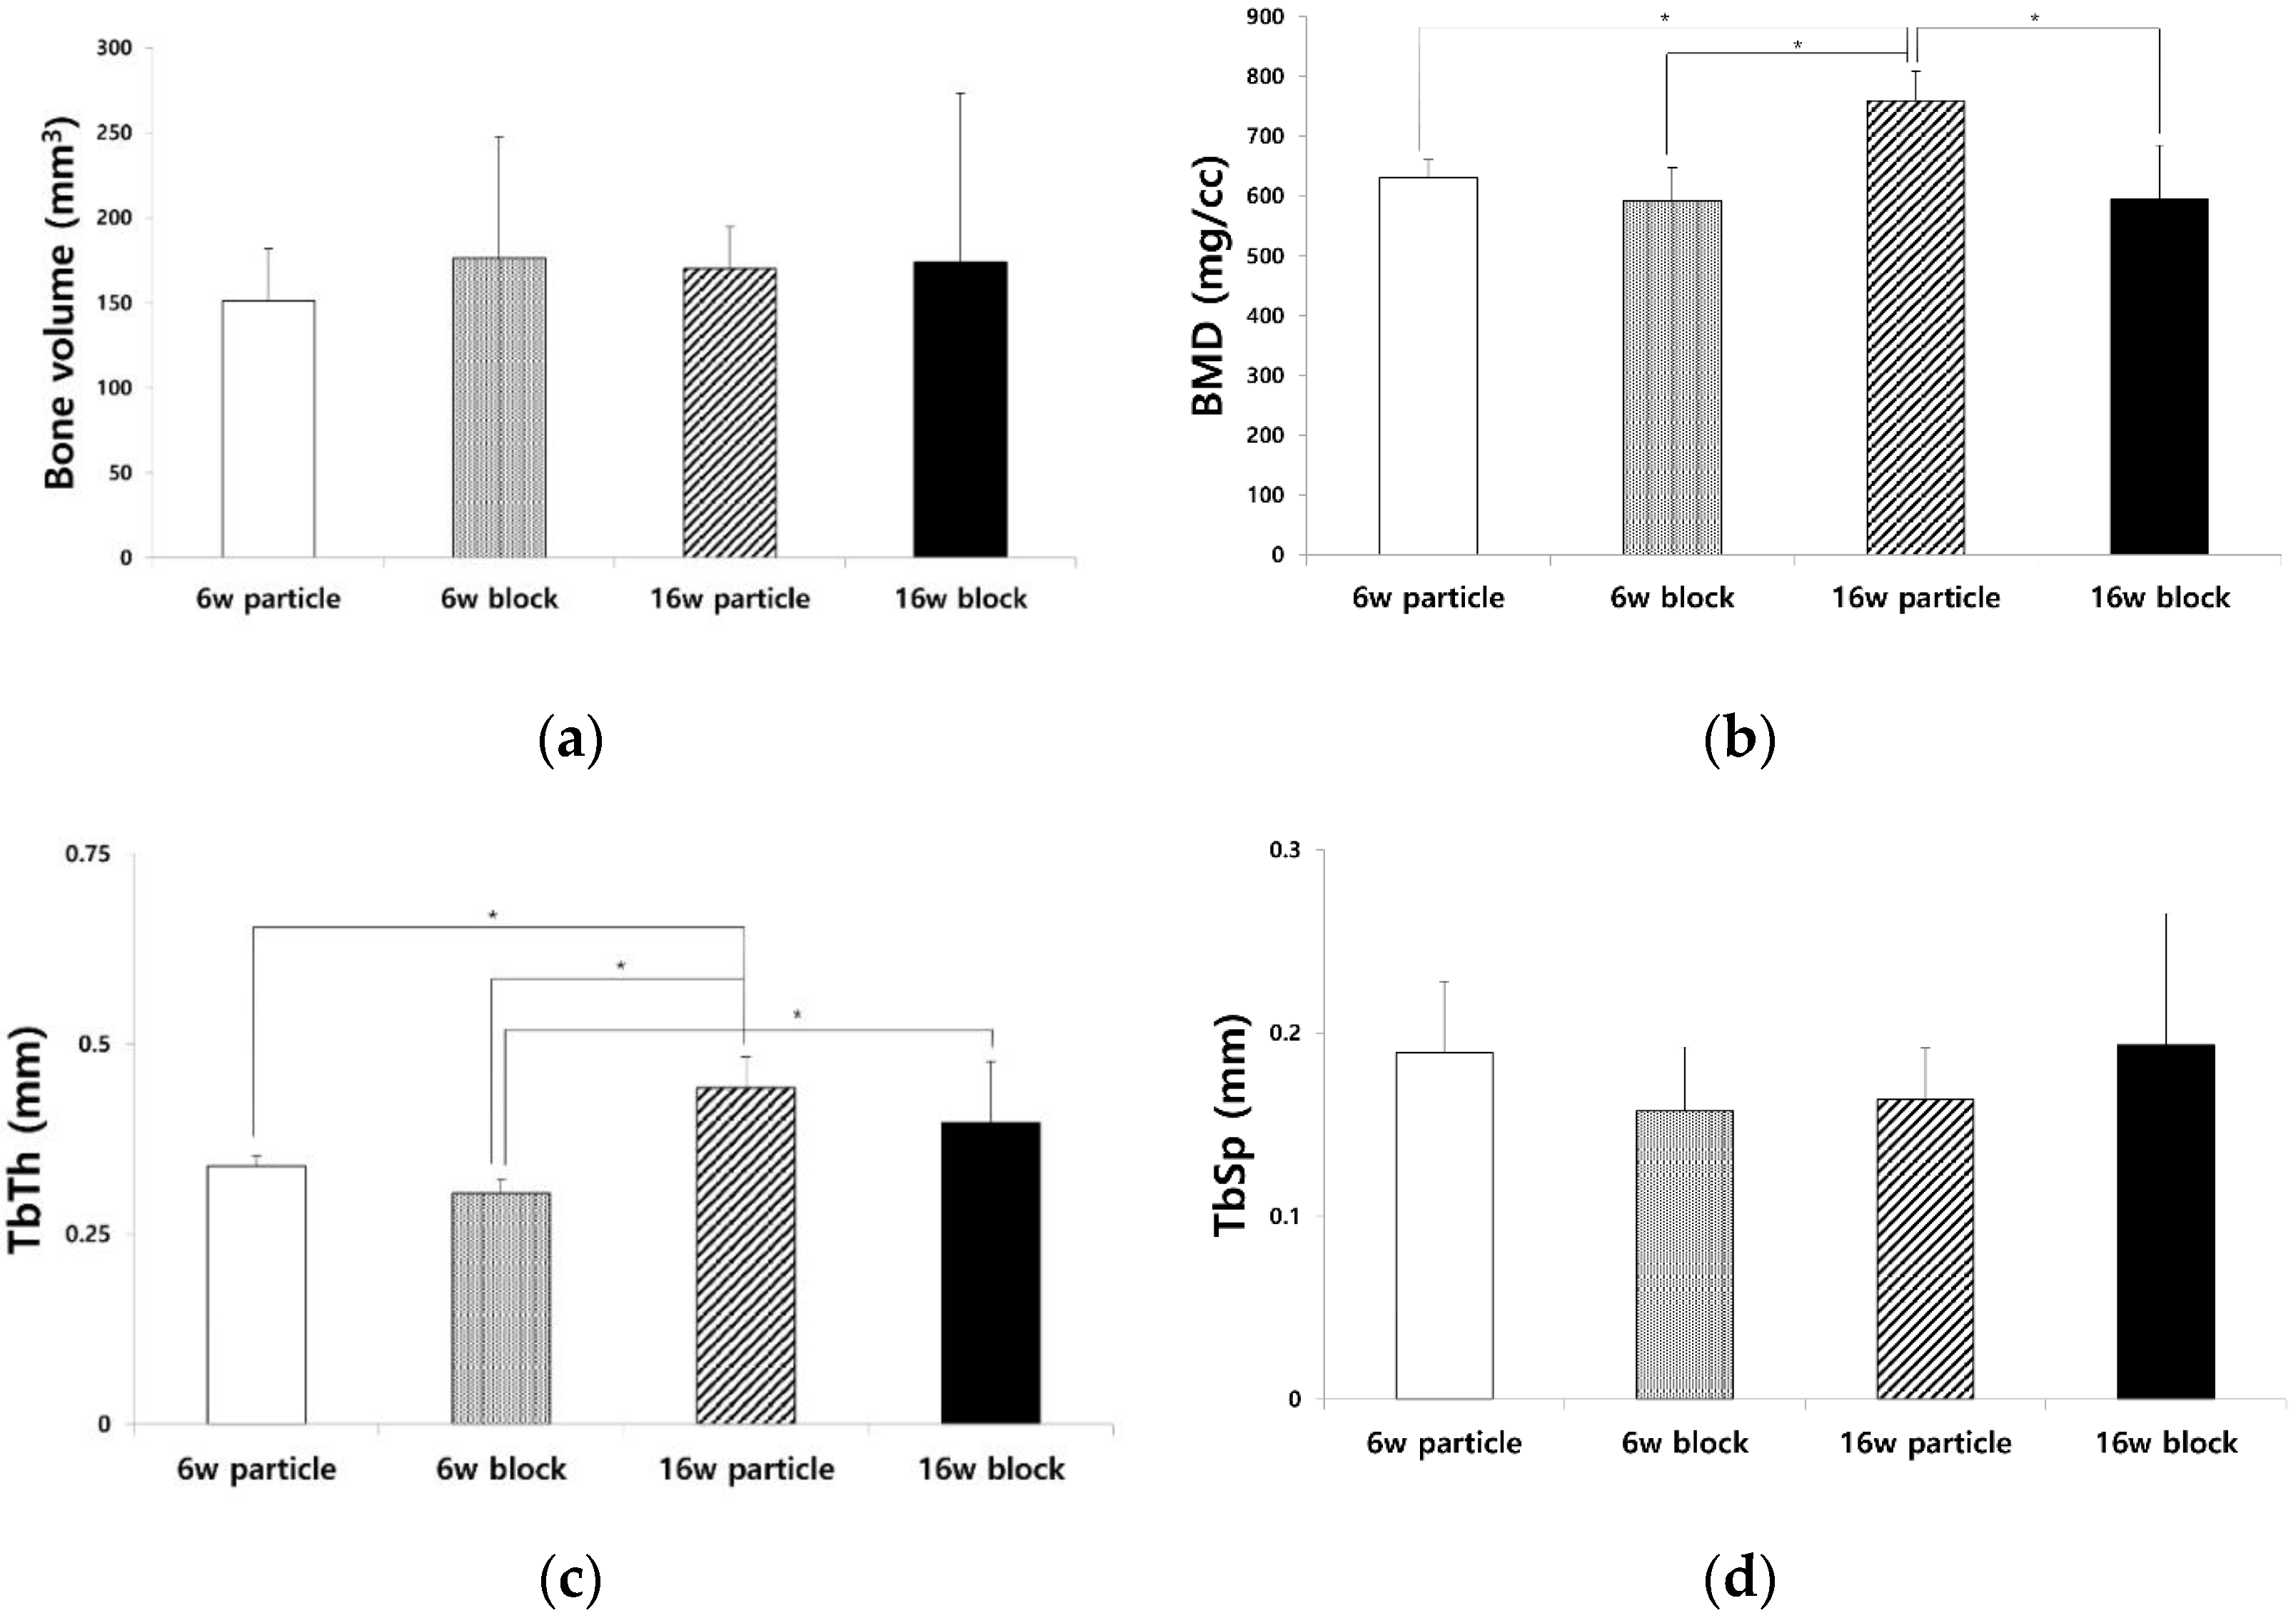

3.1. μ-CT Analysis of BV, BMD, TbTh, and TbSp